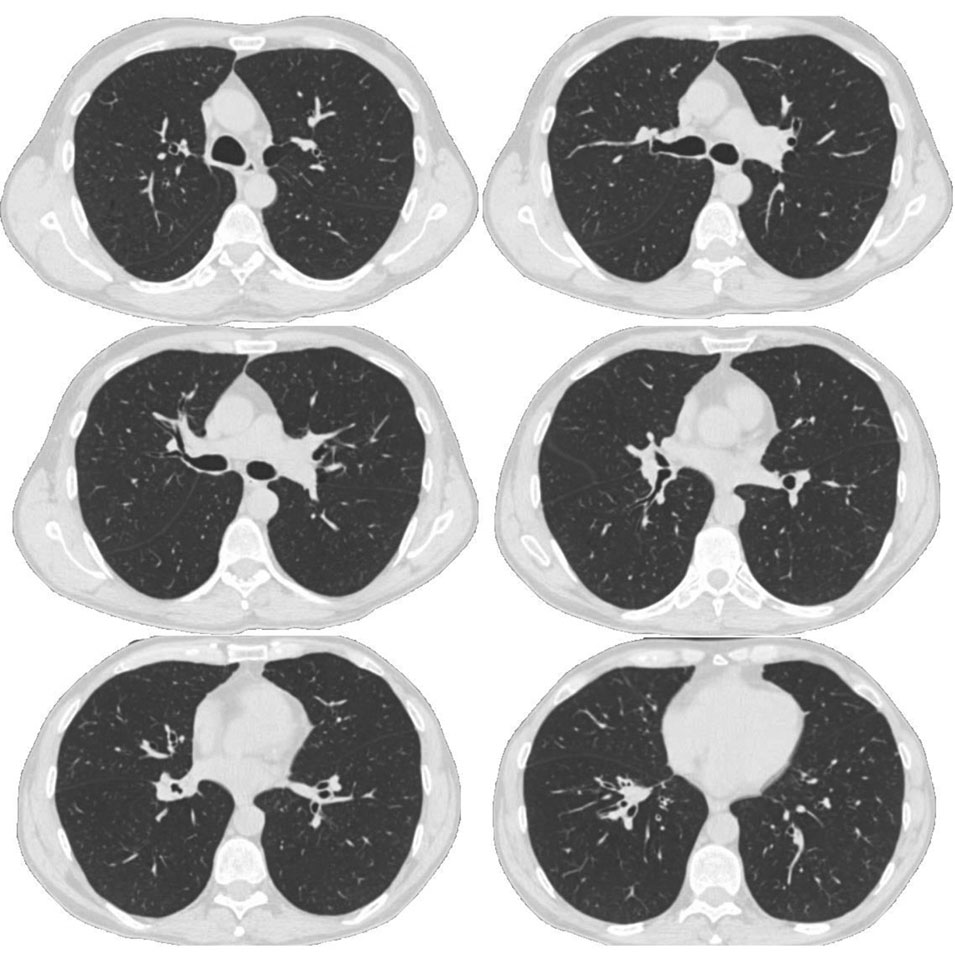

Проведены 3 курса химиотерапии (через месяц после оперативного вмешательства) по схеме: паклитаксел + + цисплатин, осложнившиеся полинейропатией 2–3-й степени и болевым синдромом в костях 2-й степени, слабостью 2-й степени. На рисунке 2 представлены результаты СКТ ОГК от 18.05.2021 г.: в области культи средне- и нижнедолевых бронхов узловых образований не выявлено, верхняя доля расправлена; в правой плевральной полости жидкость толщиной слоя 12 мм; в верхних долях обоих легких центрилобулярная и парасептальная эмфизема; в S10 слева кальцинированные очаги до 2 мм; в легких плотные полиморфные очаги до 4 мм без динамики, вероятно фиброзного генеза; лимфоаденопатия не выявляется. Исследование проводилось в период проведения химиотерапии.

Рис. 2. Спиральная компьютерная томография органов грудной клетки пациента В. после билобэктомии в период проведения химиотерапии

Fig. 2. Spiral computed tomography of patient B’s chest organs after bilobectomy during chemotherapy